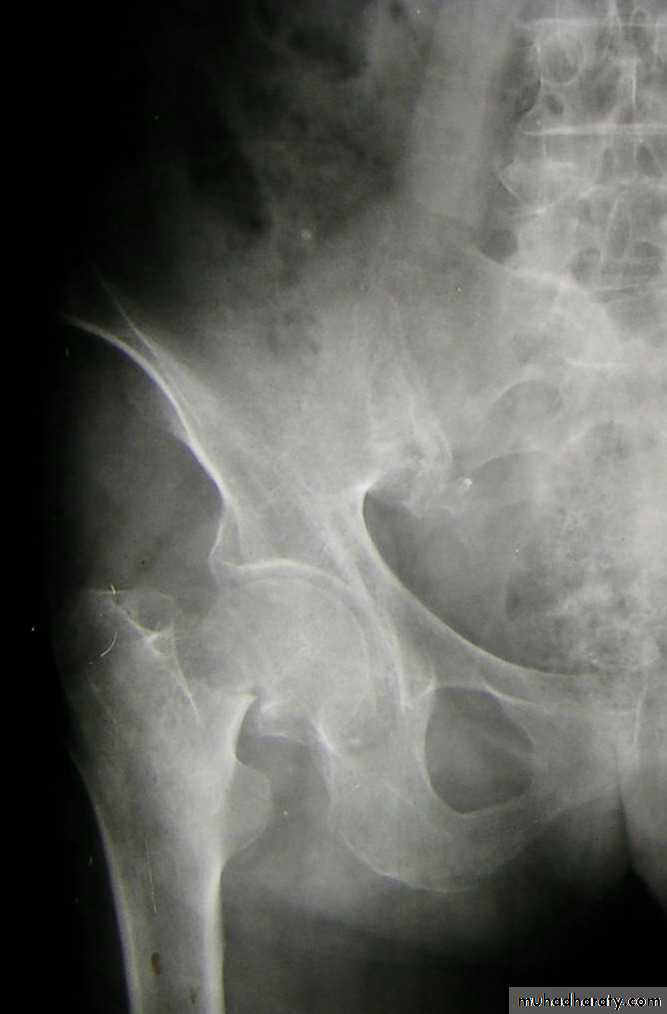

Inter-trochanteric fractures (extracapsular fracture)

.It is extra capsular fracture occurs in elderly.

.Unite quite easily and seldom cause a vascular necrosis.

Pathological anatomy divided into:

Stable:

Lower limbs

Unstable are those where

a. posteriomedial cortex is shattered.

b. poor contact between fracture segment.

Radiological examination

2 types

Stable.

Unstable.